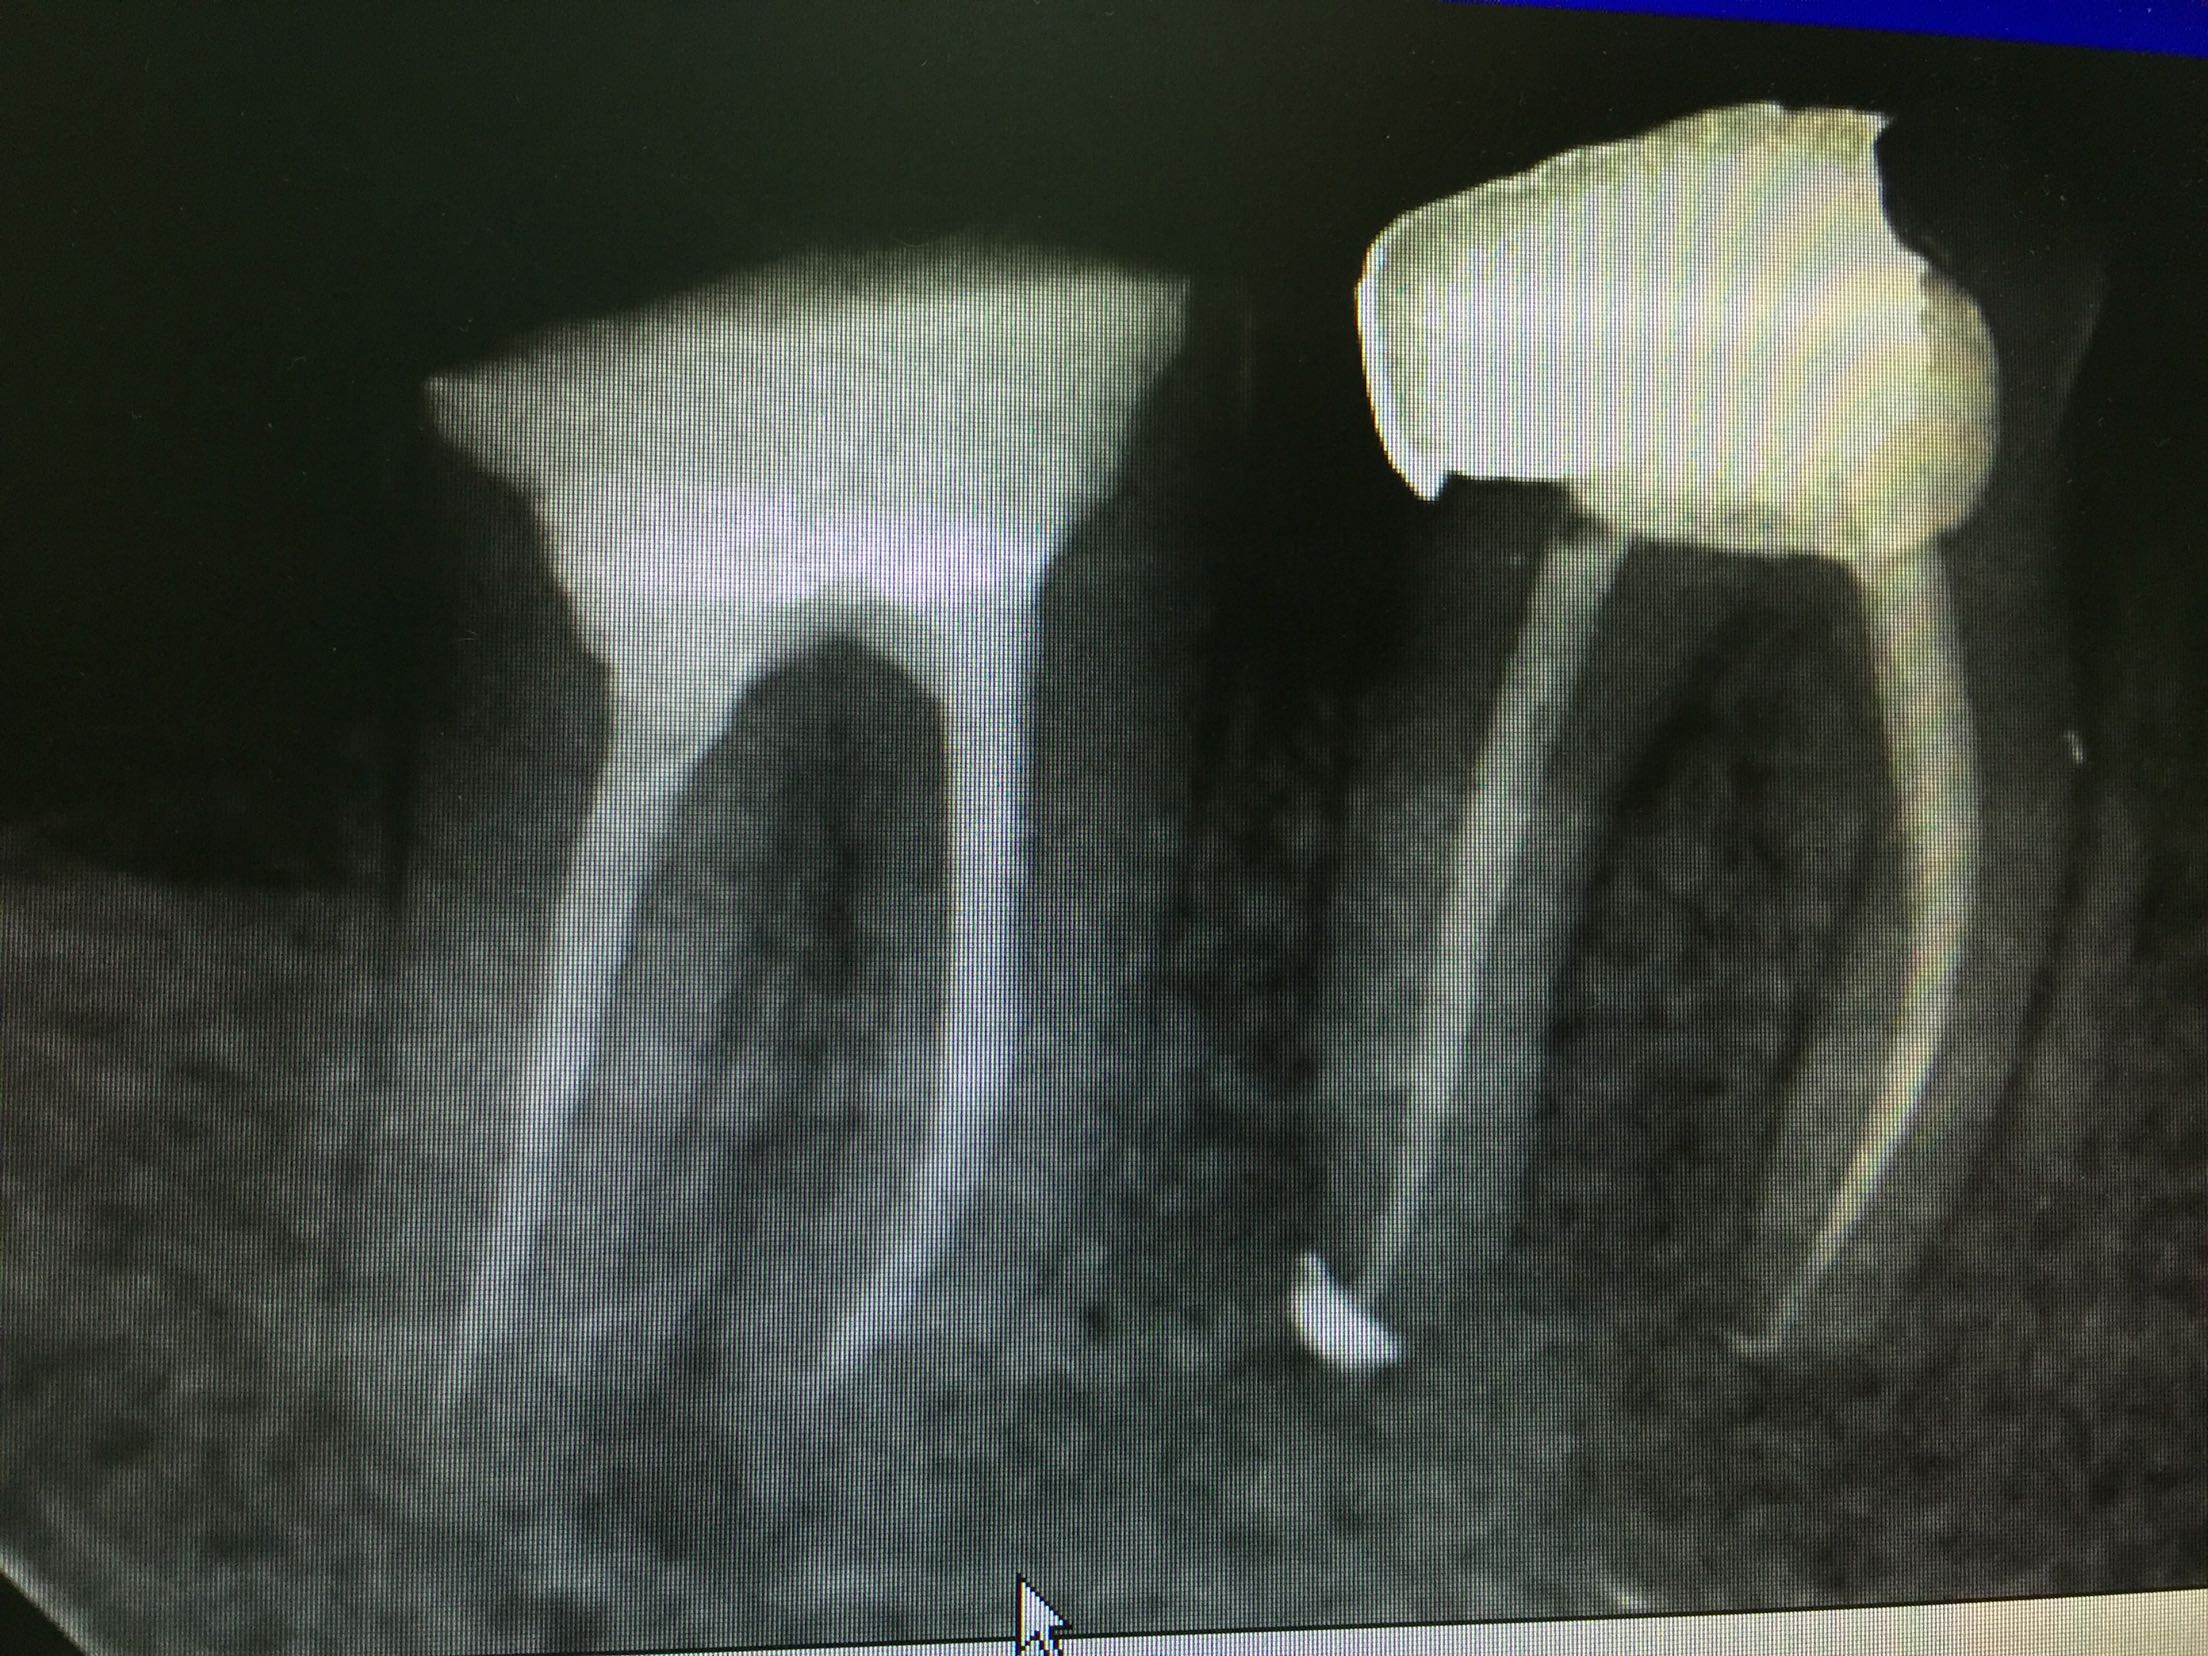

检查:47充填物存,46牙备后,充填物存,叩诊(+-),松动不明显,牙龈无明显红肿,冷诊(-)。X线示:46根尖区低密度影像,根充欠充,不密合。47根充后影像,根充可。

诊断:46慢性根尖周炎 治疗:46常规去除原充填物,拆根充,分步完成根管治疗。 转修复科进一步行修复治疗。